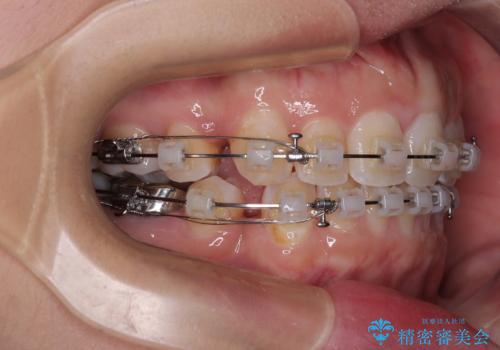

- 矯正装置

- クリアブラケット

- 治療期間

- 2年

奥歯の虫歯は事前に矯正治療用の仮歯に置き換えて矯正治療を行い、装置除去後にセラミッククラウンにて補綴治療を行うこととしました。

通常は上下左右の第一小臼歯4本を抜歯することになりますが、左側下顎の第二小臼歯は既に根管治療をされており、予後が良くないとのことでこの歯を抜歯し、ワイヤー装置にて矯正治療を行うこととしました。

第二小臼歯抜歯はイレギュラーな治療手段であり、治療期間が延びる傾向にありますが、予定よりも早い2年間で終えることができました。